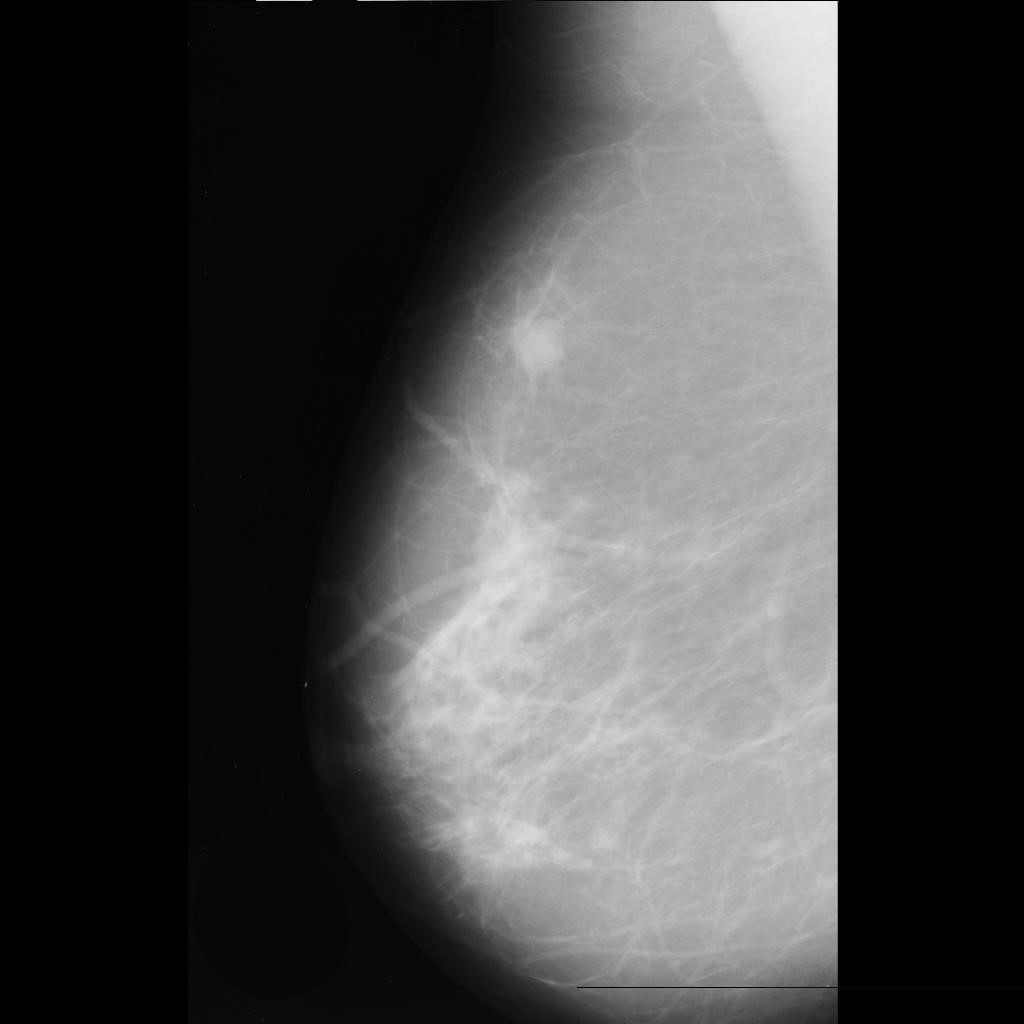

malignant